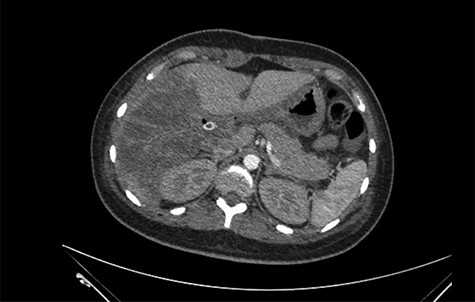

She was referred to our center on postoperative Day 4 due to progressive jaundice and encephalopathy. A triphasic contrast-enhanced abdominal computed tomography (CT) was done revealing a right liver lobe infarct, absence of the right and left hepatic arteries (Fig. 1), presence of an accessory left hepatic artery from the left gastric artery (Fig. 2) and right portal vein thrombosis with extension to the main portal vein (Fig. 3).

Main portal vein thrombosis (white arrow) on portal phase of the triphasic contrast-enhanced abdominal CT.